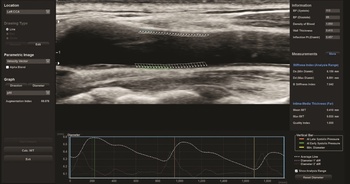

A sugárterheléssel nem járó ultrahangvizsgálatokat számos területen alkalmazzák az ikerkutatásban (1. és 2. a, b ábra), a policisztás ovárium szindrómától kezdve a szaruhártya megítélésén át az érelmeszesedés vizsgálatáig széleskörűen alkalmazott módszer. Néhány ultrahangos ikervizsgálatot emelnénk ki ezek közül. A finn ikerregiszter hüvelyi ultrahang vizsgálattal ítélte meg a méh gyakori jóindulatú daganata, a mióma előfordulását. A miómák száma gyenge genetikai meghatározottságot igazolt, míg a miómák előfordulása összefüggést mutatott a magasabb testsúly-testmagasság indexszel (Luoto et al., 2000). A fejlődő országokban egyre gyakrabban előforduló epekövesség molekuláris patogenezise nem teljesen ismert. A svéd ikerregiszter munkatársai epekövességben szenvedő ikerpárok – részben ultrahangos – vizsgálata során kimutatták, hogy az ABCG8 D19H génvariánst hordozó egyéneknek nagyobb az epekövességre való hajlamuk (Katsika et al., 2010). A hazánkban is minden negyedik felnőttet érintő nem alkoholos zsírmáj hátterében additív genetikai hátteret nem igazolt vizsgálatunk, közös (74,2%) és egyéni (25,8%) környezeti tényezők állnak a betegség hátterében (Tárnoki et al., 2012). Szintén hazai ikermintánkon ultrahanggal vizsgáltuk a veseparenchima vastagságában szerepet játszó genetikai meghatározottság mértékét, mely korra és nemre korrigálva 0%-os volt, a közös (30%) és egyéni (70%) környezeti tényezők hatásai domináltak. Eredményeink az életmód, illetve a primer prevenció fontosságára hívták fel a figyelmet (Tárnoki et al., 2013).

1. ábra. Magyar ikeralany pajzsmirigy ultrahang elasztográfiás mérése, melynek során a göbök elaszticitási indexét vizsgáltuk